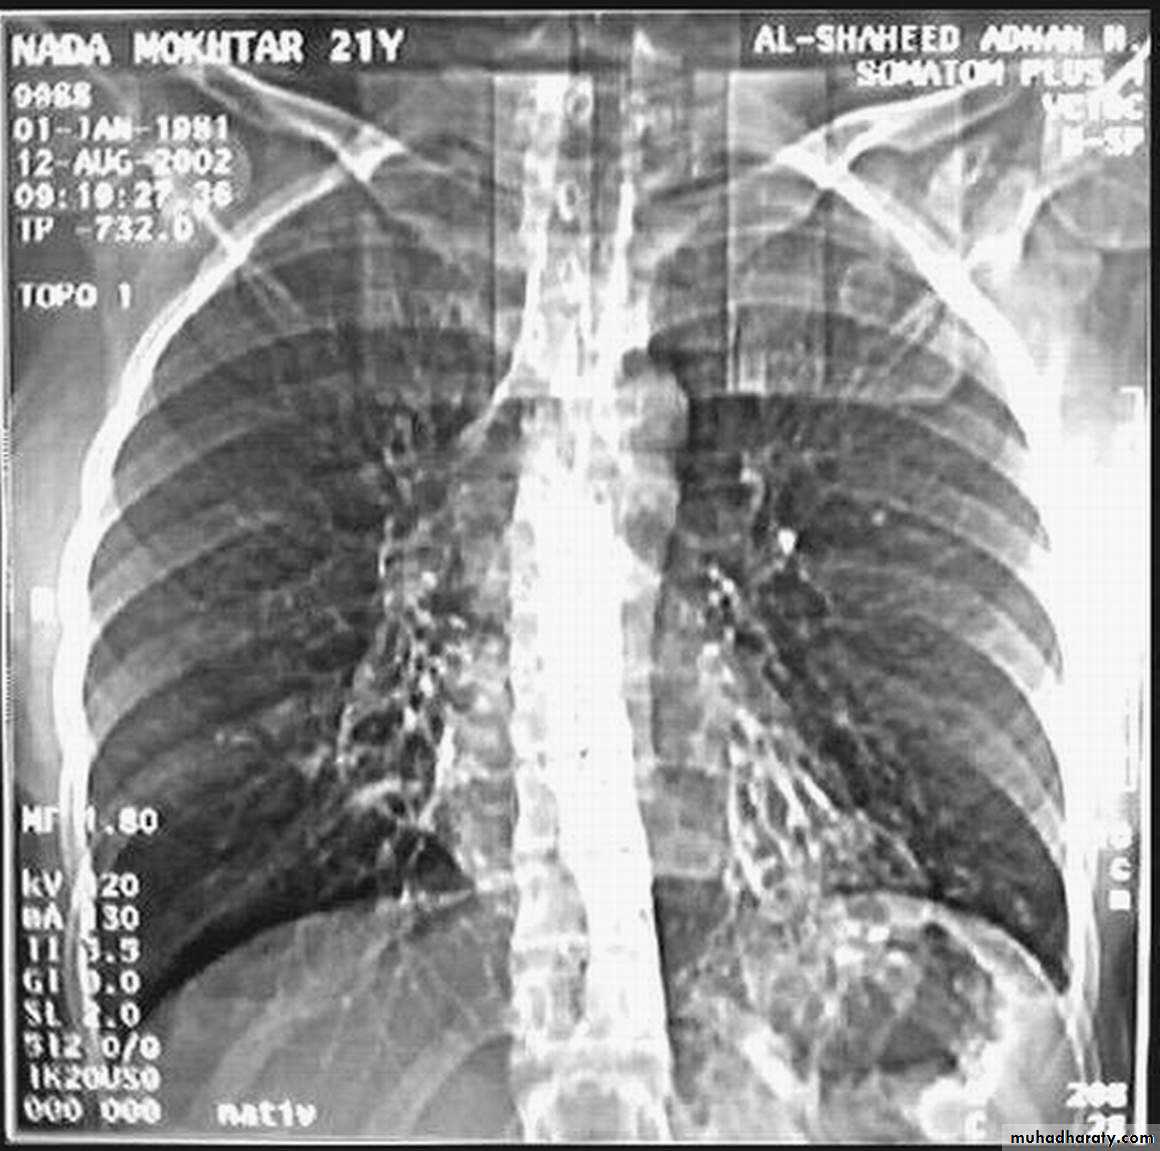

Bronchogenic Ca. cavitory lesion

• Pathology :-A-Central type is the commonest (75%).It arises in one of the main bronchi or their primary division leading to bronchial obstruction with secondary changes in the lung such as atelectasis .B-Peripheral type (25%) arises from the smaller bronchi and remains symptom less for long time .

• Chest X-ray ,CT chest ..